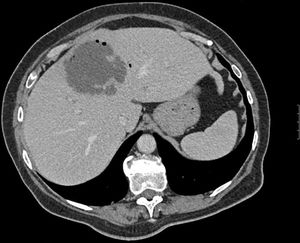

Mujer de 70 años hipertensa, diabética y con cardiopatía hipertensiva, que consulta por dolor en hipocondrio derecho de 2 semanas de evolución, fiebre y vómitos. Presenta fracaso renal e hipotensión refractaria. La TC urgente evidencia una colecistitis aguda litiásica con un absceso hepático de 13cm. Se realiza drenaje percutáneo urgente ecoguiado en quirófano, iniciando antibioterapia y soporte hemodinámico. Tras buena evolución clínica, es dada de alta al décimo día (figs. 1 y 2).